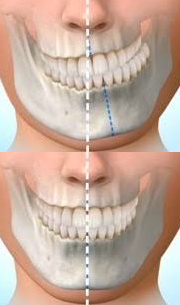

顎変形症とは別に、【顎偏位症】という病名があります。

顎偏位症とは、

下顎(かがく)の位置が、正常な位置からわずかに偏っている状態を、「顎偏位症」(がくへんいしょう)といいます。

顎偏位症は、「顎変形症」や、「顎関節症」(がくかんせつしょう)とは異なります。

顎偏位症は骨がズレている骨格性の為、矯正治療ではお顔の歪みを改善することはできません。